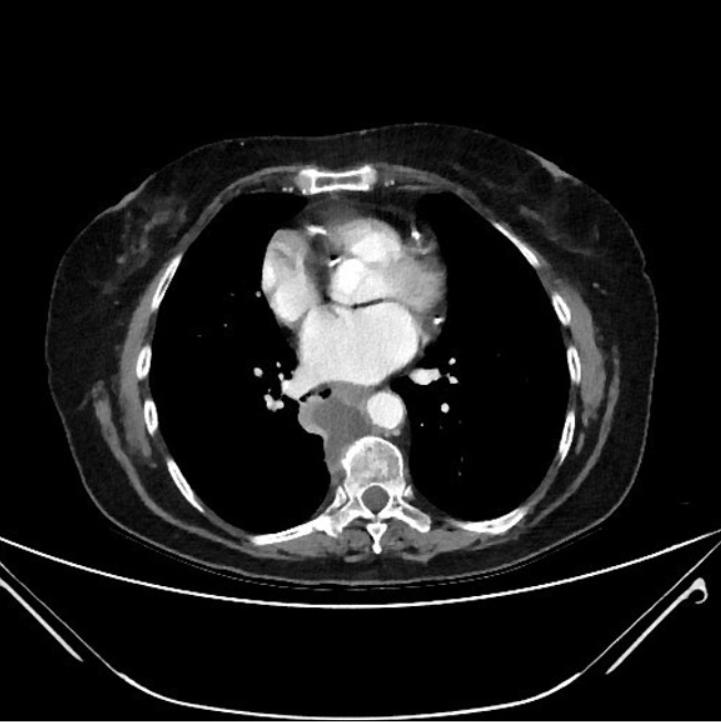

2020年4月3日胸部CT显示,右下叶后段(背段)有一个4.3cm×4.7cm的肿块,中心坏死,紧邻胸主动脉和食管。CT引导下肺部肿块穿刺活检证实为低分化鳞状细胞癌,PD-L1在50%的细胞中表达。

PET-CT扫描显示右下叶显著(18)F-氟脱氧葡萄糖摄取,标准摄取值(SUV)为13.6,右肺门摄取小焦点,标准摄取值为3.5(图1)。

图1脑部磁共振显示没有转移,支气管内超声和纵隔淋巴结活检显示纵隔淋巴结未受累。患者器官功能非常好,东部肿瘤协作组评分(ECOG评分)为1。